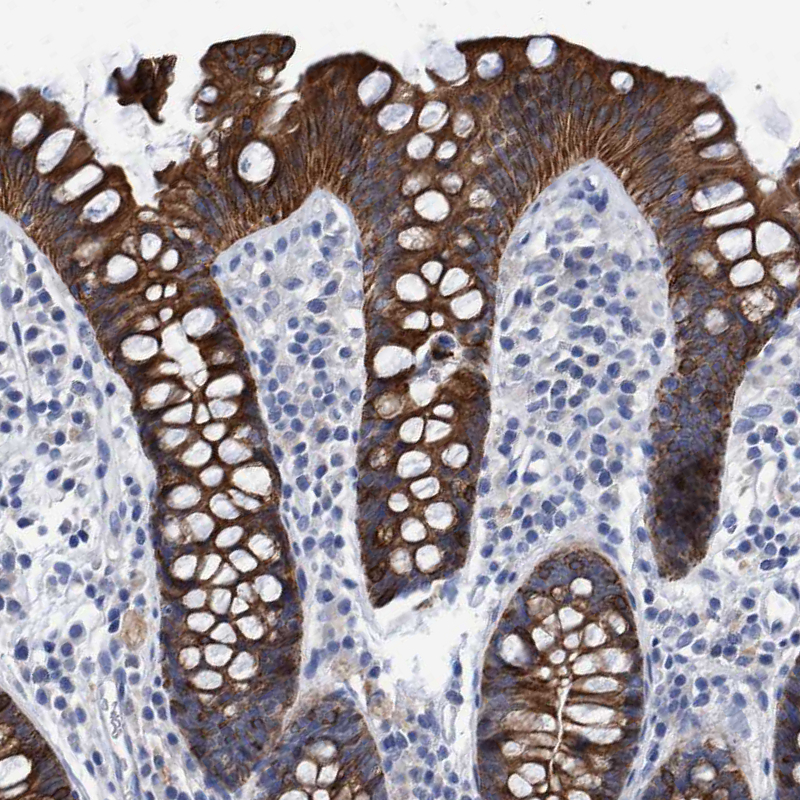

Immunohistochemical staining of human colon, fallopian tube, kidney and liver using Anti-MKS1 antibody HPA021812 (A) shows similar protein distribution across tissues to independent antibody HPA021372 (B).